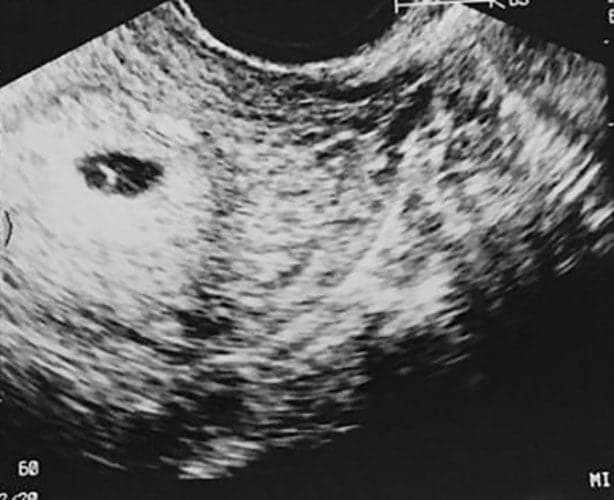

Ultraschallbilder aus dem 1. Trimester (1. SSW bis 12. SSW)

Im ersten Trimester sind die Ultraschallbilder meist noch schwer zu deuten. Oft erkennt man in den letzen Wochen des ersten Trimesters gut den Körper, den Kopf und die Gliedmaße. Das Geschlecht kann man in dieser Zeit meist noch nicht erkennen.